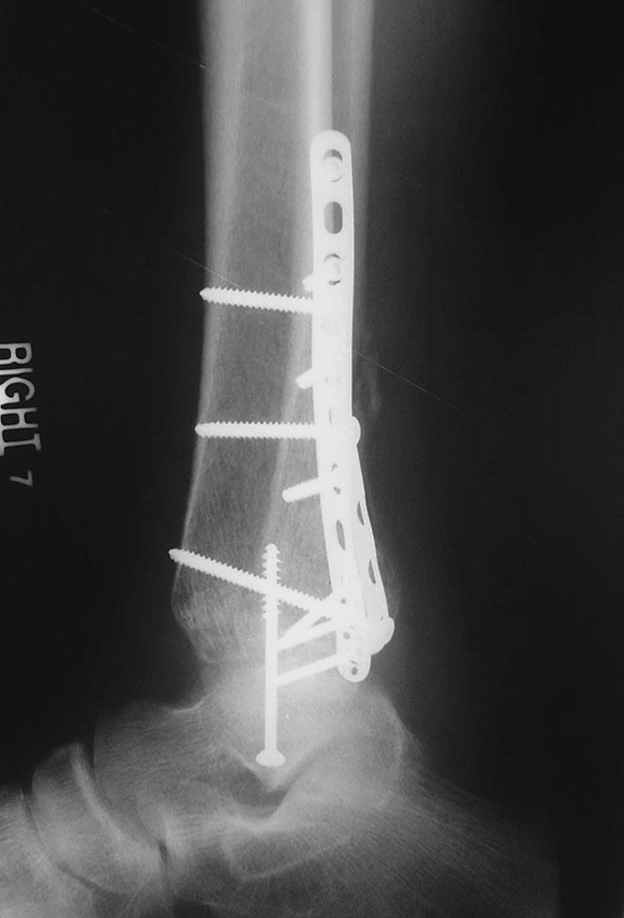

Второй случай сделан из одного разреза

Дж

ЕЧ LISS plate, mininvasive approach - luxurous !

На прямой проекции послеоперационного Рг макроскопически все выглядит очень анатомично, при микроскопическом ( :-)) ) рассмотрении можно все-таки заметить вальгизацию тарана, суставная щель в латеральном отделе сустава несколько уже , чем в медиальном при отсутствии латерального смещения тарана. У меня был аналогичный случай (без LISS , без мини доступа) с вальгусным наклоном тарана при восстановленном ankle mortise при последовательном наблюдении с интервалами в 6-8 недель в послеоперационном периоде отмечалось прогрессирующее сужение суставной щели в латеральном отделе сустава, закончившееся посттравматическим ОА, к счастью боли умеренные, купируемые аналгетиками или своими эндорфинами:-))(активная пациентка, у которой нет времени на болезни....) Какова жизненная ситуация в приведенном вами случае? И последнее, что я хотел бы прояснить для себя - фиксация внутренней лодыжки: я обычно комбинирую фиксацию компрессирующим винтом со спицей - по идее ротационная стабильность должна быть лучше, чем один винт, каковы ваши наблюдения в этом плане?